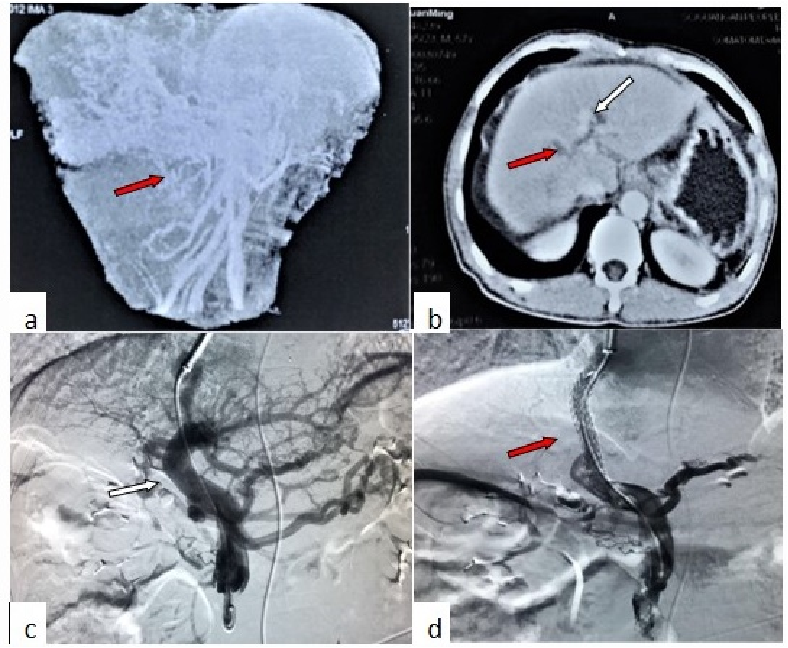

与粗大门静脉侧枝行TIPS (肝硬化基础PVT)